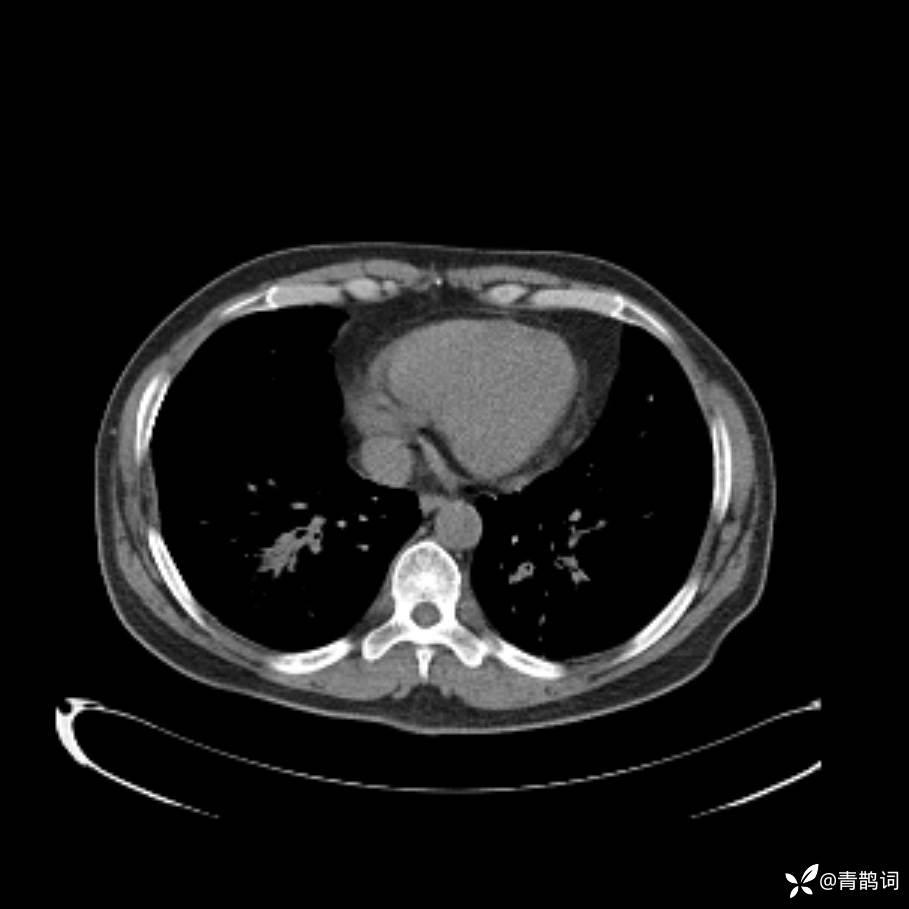

患者年龄:30岁。

患者性别:男。

简要病史:左颜面部肿胀2年,反复咳嗽咳痰,逐渐加重。

辅助检查